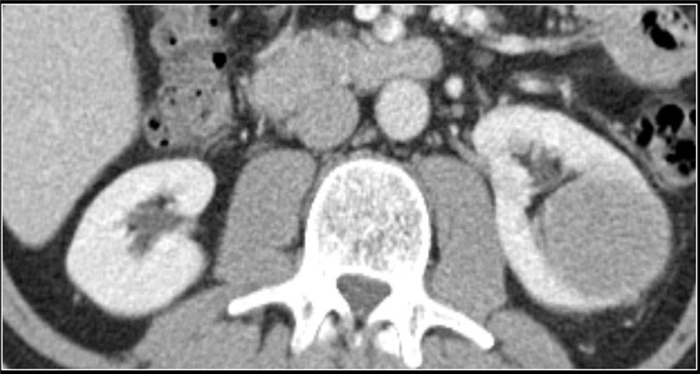

(Слева) КТ с контрастированием, коронарная проекция: у женщины 32 лет, поступившей с болью в боку, лихорадкой и позитивным бактериальным посевом крови на Е. coli, выявлены гематогенные стафилококковые абсцессы левой почки и левой поясничной мышцы.

(Справа) КТ с контрастированием, аксиальная проекция: у этой же пациентки визуализирован чрескожный дренажный катетер внутри абсцесса почки. После дренирования отмечено полное восстановление.